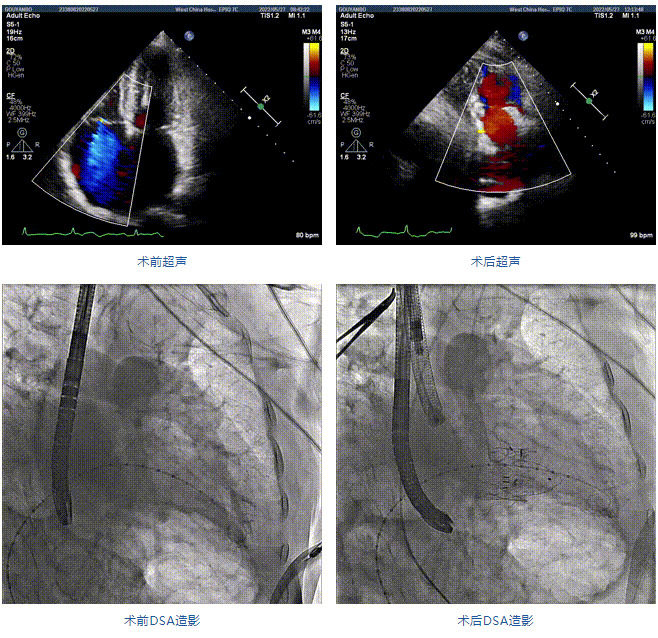

89歲男性。術(shù)前超聲報告顯示:雙房增大,左室壁肥厚,主、肺動脈增寬,三尖瓣重度反流。

團(tuán)隊前期經(jīng)過多次討論,制定了周密的手術(shù)策略和預(yù)案。由于患者已是近九旬的超高齡老人,傳統(tǒng)外科開胸手術(shù)風(fēng)險極高,純介入經(jīng)血管三尖瓣替換能夠明顯減少創(chuàng)傷。術(shù)中陳茂及馮沅教授結(jié)合體表定位在造影指示下精準(zhǔn)穿刺右側(cè)頸靜脈并預(yù)置兩把血管縫合器。成功建立經(jīng)皮血管入路后在食道超聲和DSA的引導(dǎo)下順利完成人工瓣膜植入,術(shù)后超聲和造影顯示人工三尖瓣同軸性良好,瓣架固定牢靠,無反流和瓣周漏,平均跨瓣壓差降為1mmHg。術(shù)畢收緊預(yù)置的血管縫合器縫線完成止血,縫合效果滿意,在手術(shù)室即刻拔除氣管插管。